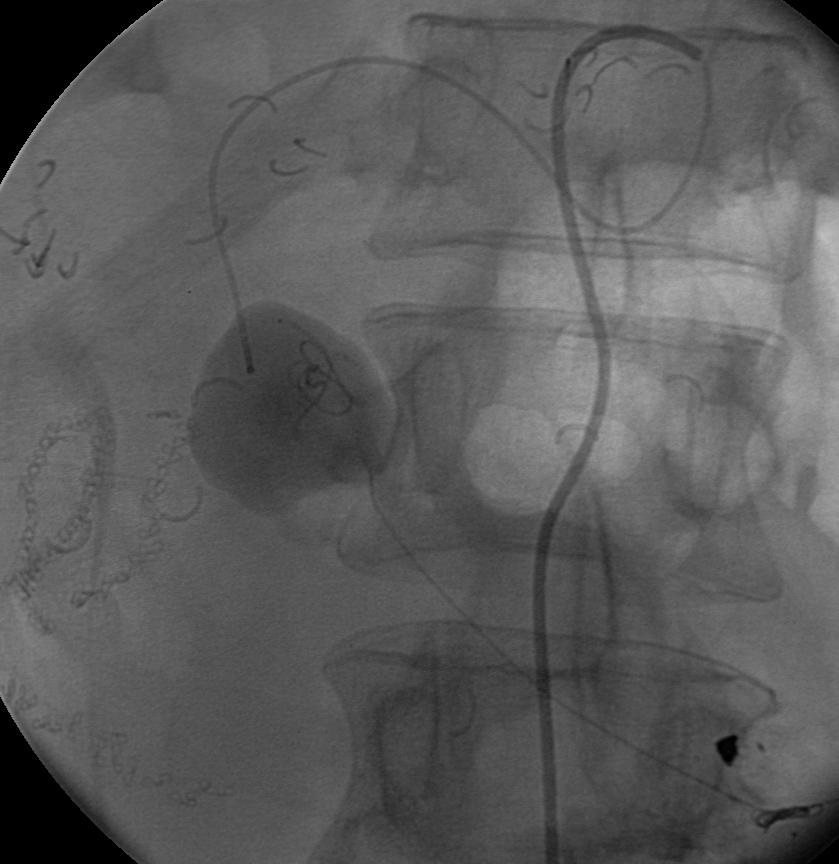

胰十二指肠动脉瘤占内脏动脉瘤2%。主要原因包括动脉硬化,腹腔动脉狭窄等疾病,后者是由于胰腺动脉弓的高血流状态(Sutton and Lawton 1973)。假性动脉瘤主要由于胰腺炎、创伤和感染(Suzuki et al. CVIR 2008;31:1082-1087)。 腹腔动脉闭塞导致胰腺血管弓

腹腔动脉闭塞导致胰腺血管弓的高血流状态致使胰腺动脉明显增粗 |

Suzuki 等人报告7例CT证实破裂动脉瘤病人,平均直径0.6mm。破裂与大小没有直接联系,18%的破裂动脉瘤<1cm。一般推荐在发现时就进行血管内治疗,但要考虑解剖情况和技术上的困难。